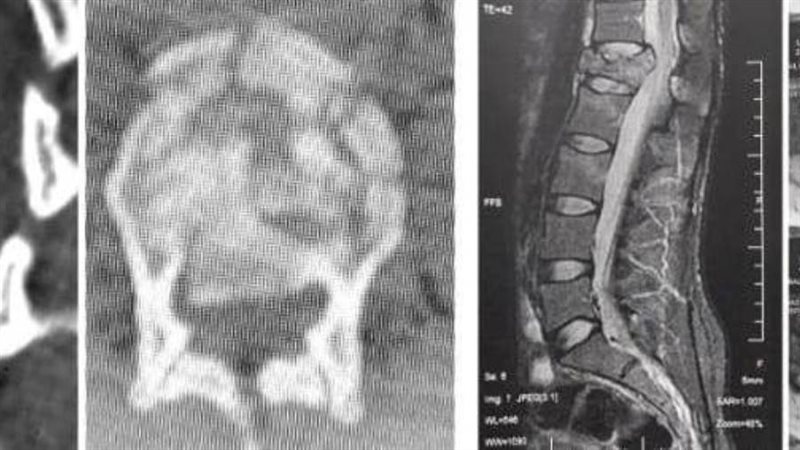

وأعلن الدكتور تامر حمدى أحمد مدير عام المستشفى في بيان ) عن قيام الدكتور صلاح صبرى محمد صلاح مدرس مساعد جراحة المخ والأعصاب بمستشفيات جامعة الزقازيق .. يرافقه الدكتور محمود الوكيل مدرس التخدير بالقصر العينى جامعة القاهرة .. بإجراء جراحة عاجلة لمريضة تعانى من كسر في الفقرة القطنية الأولى ضاغط على الحبل الشوكى .. مما نتج عنه ضعف في حركة الطرفين السفليين ، وأنه على الفور تم عمل الاشعات اللازمة للمريضة ودخولها غرفة العمليات لتثبيت الفقرات الصدرية والقطنية بواسطة شرائح ومسامير وتوسيع القناة العصبية وإزالة الضغط على الحبل الشوكى .. مشيرا الى استمرار الحالة بالمستشفي حتى استقرت وتحسنت حركة الطرفين السفليين لها .